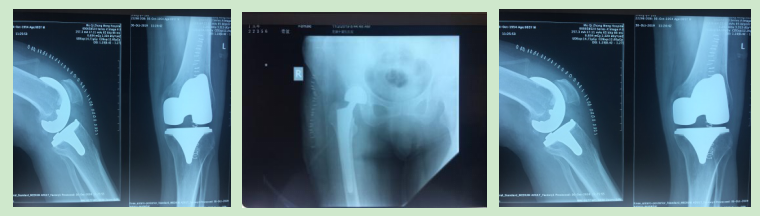

参与完成全膝关节置换术、髋关节置换术、胫腓骨骨折钢板螺钉取出术、踝关节骨折钢板螺钉取出术及清创缝合术等手术六例。